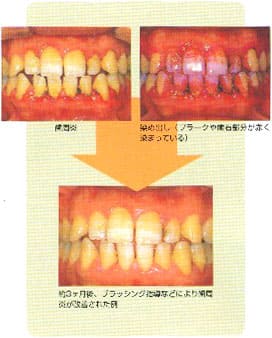

歯周病の予防と治療には、 ブラッシシグ(歯磨き)で口腔内を清潔に保つことが基本の基本です。

歯周病やむし歯の原因は、プラークです。このプラークは、ていねいなブラッシングによって、大部分取り除くことができます。 つまり、適切なブラッシングをつづけることで、歯周病を予防することができるのです。 それだけではありません。程度の軽い歯周病であれば、ブラッシングで治してしまうことも可能です。